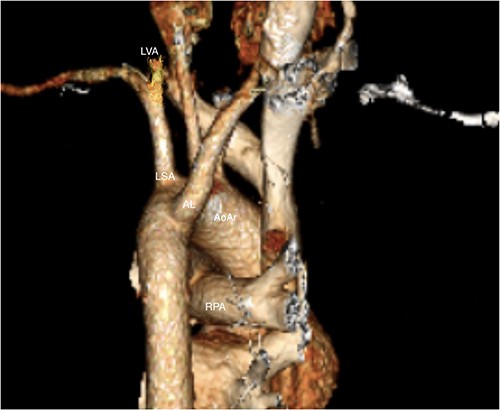

In this patient’s case, the above approach was not deemed possible. The origin of the aberrant subclavian artery was too close to the origin of the left subclavian artery to achieve a safe landing zone and graft seal without compromising supply to the latter. Of note, the patient had a very dominant left vertebral artery, supplying the majority of their postero-basilar circulation (Fig. 1).

LVA: Left vertebral artery, LSA: left subclavian artery, AL: arteria lusoria, RPA: right pulmonary artery, AoAr: aortic arch.